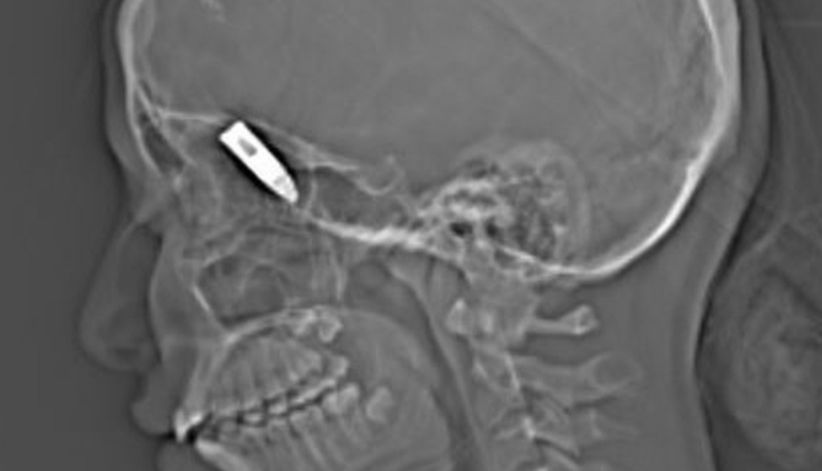

Foto rontgen memperlihatkan proyektil peluru di kepala anak perempuan di Saudi (Foto: Khaleej Times)

Dokter berhasil mengeluarkan proyektil dari tempurung kepala korban. Peluru bersarang di sebelah kiri dekat mata.

Setelah diambil, diketahui panjang peluru tajam itu tiga sentimeter.